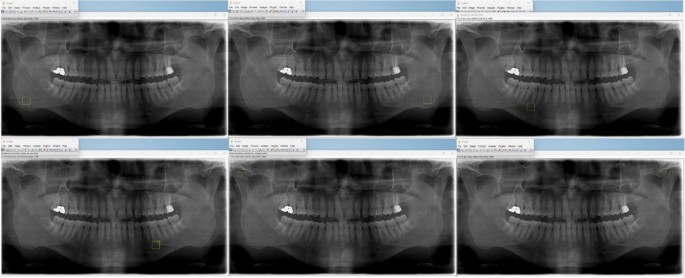

Panoramic radiograph reveals mandibular cortical width and other... | Download Scientific Diagram

Mandibular cortical width measurement (MCW). ( A ) Graphic... | Download Scientific Diagram

Medidas de Índice Cortical Mandibular realizado bilateralmente cerca... | Download Scientific Diagram